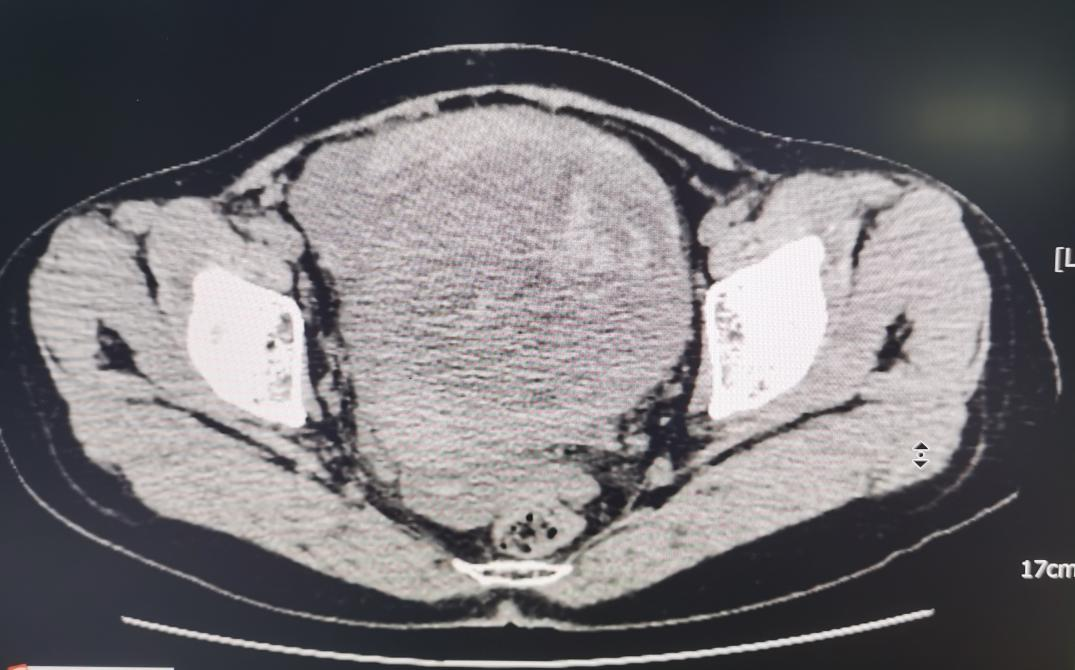

患者为40岁女性,平时没有体检的良好习惯,近日因“下腹痛6小时,晕厥2次”由外院转入我院急诊科,外院妇科超声提示患者有一巨大的子宫肌瘤,我院急诊盆腔CT提示患者存在大量腹腔内出血及子宫占位性病变破裂出血的可能。妇产科住院总李燕辉主治医师和妇科当班医生曾秋兰主治医师接诊后对患者进行了腹腔内穿刺,抽出不凝血证实了患者的腹腔内出血,初步考虑引起出血的原因是常见的卵巢黄体破裂或异位妊娠破裂,其他问题也还有待排查。情况刻不容缓,急诊科团队马上与患者及其家属谈话经绿色通道手术探查,并立即汇报妇产科学科带头人胡洁媚和妇产科主任李克红进行急诊手术。

术前盆腔CT截图

术中发现这名患者并非是因为常见问题导致的腹腔内出血,而是罕见的子宫肌瘤破裂出血。子宫肌壁间突出于浆膜层的肌瘤大小约10x9cm,肌瘤左侧壁见一破裂口大小约2x2cm,见较多的新鲜活动性出血。术中与患者家属再次谈话后决定行子宫肌瘤切除术,术后患者恢复良好,病理结果为:子宫平滑肌瘤坏死、出血、粘液样变及玻璃样变。